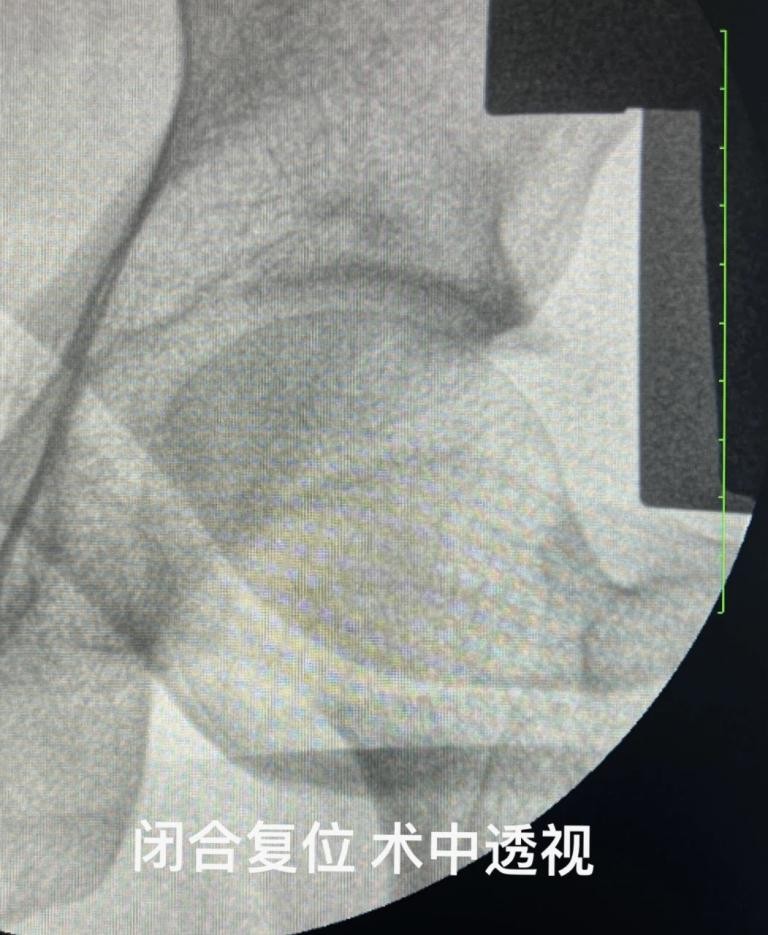

面对如此复杂的伤情,叶博士及其团队迅速展开讨论。传统开放复位内固定手术虽能直视骨折部位,但对周围组织损伤较大,且难以兼顾股骨头血供保护。经过反复斟酌,团队决定采用一种创新的治疗方法——数字化设计的缝匠肌内侧入路可吸收棒固定术。

这种术式以缝匠肌为解剖标志,通过数字化设计辅助术前规划,明确骨折线走行及骨块空间位置,精准入路进行骨折复位与固定。相比传统术式,它具有诸多优势:清晰暴露髋关节前内侧区域,为骨折复位和固定提供良好视野,提高手术精准度;手术过程中将股神经和股动脉安全牵向内侧,最大程度避免医源性损伤,降低神经血管并发症风险;减少肌肉损伤,无需切断过多肌肉组织,有利于术后恢复,减少术后疼痛;无需截骨,直接清除血肿并原位复位,保留股骨头血供,减少术中出血、感染、异位骨化等并发症的发生,提高手术安全性。